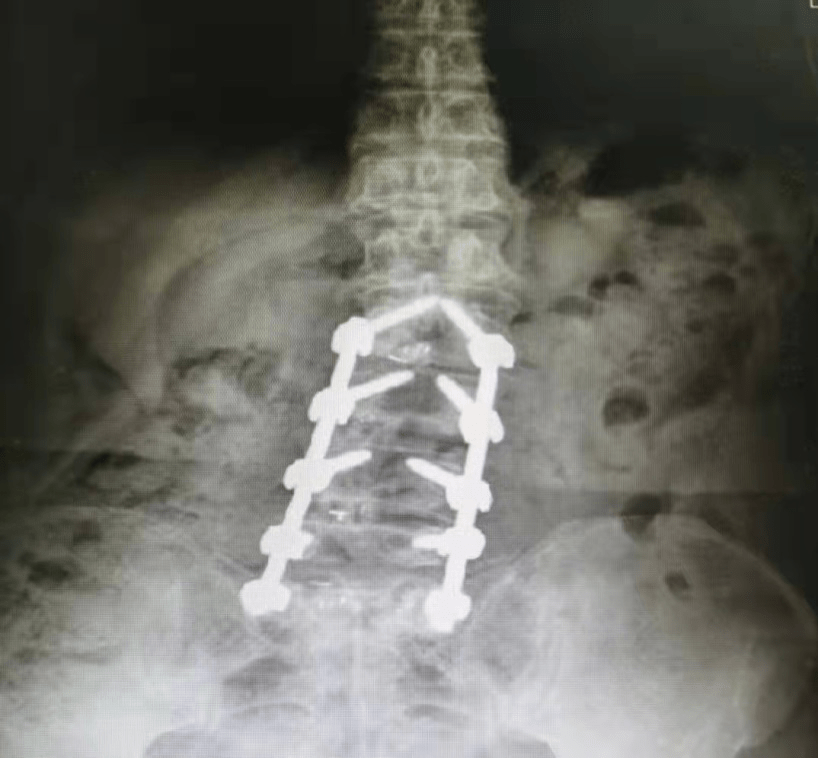

文章图片

这些年李阿姨可被这腰疼折磨坏了 , 走路疼 , 站着疼 , 坐着疼 , 躺着翻身都疼 , 严重的时候连10米都走不了 , 只能拄拐勉强站着 , 坐一会儿就腰酸得受不了 , “就像这腰不是自己的一样”为了治疗腰疼 , 李阿姨可没少去医院 , 结论基本都一样:全麻、开刀、上“钢钉钢板” , 好处是可以“从一定程度上”恢复体态 , 坏处是手术创伤比较大、风险也大 , 还不能保证手术对疼痛能有多少效果 , 因为“脊柱变形太严重、神经受压受损太久太重” 。

李阿姨的腰椎都弯了这么多年了 , 现如今这个年龄 , 对体态要求不是很高 , 主要是想解决腰疼影响生活的问题 。 可一听要全麻开刀“打钢钉” , 还不能保证对疼痛能起多少作用 , 就打起了退堂鼓 。